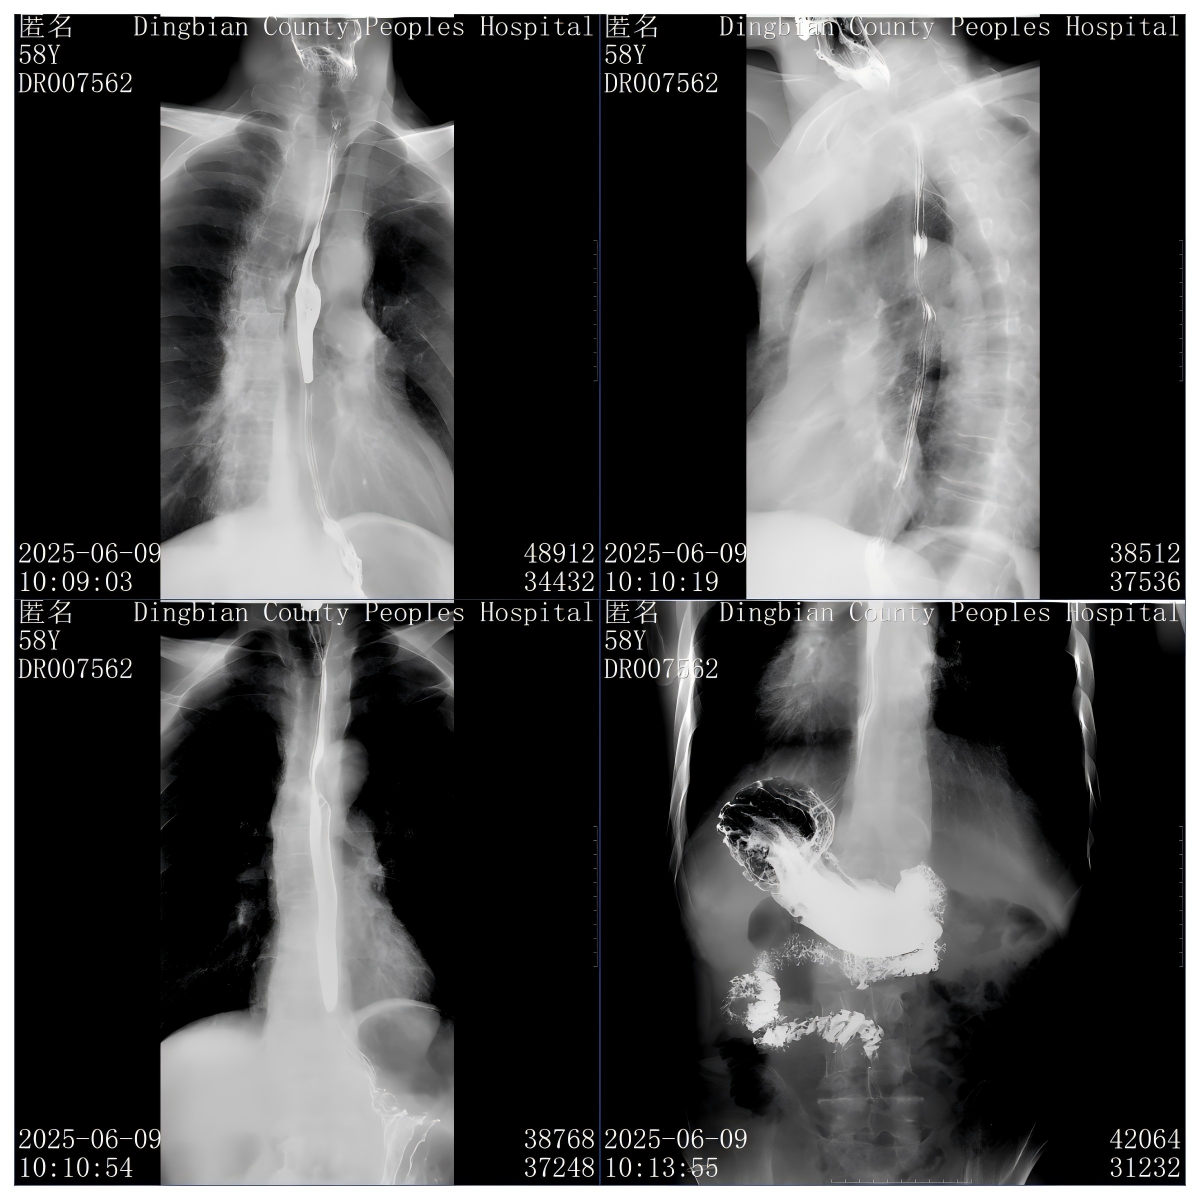

我院放射科西门子Luminos Fusion多功能化数字胃肠机,是由上海西门子医疗器械有限公司生产的通用型X射线诊断设备,适用于X射线临床摄影、透视以及外周血管DSA检查,也可用于消化道造影、胸部摄影等多种检查场景。其结构主要包括三部分:X射线发生装置(含高压发生器、X射线管组件OPTITOP 150/40/80 HC-100及限束器)、X射线成像装置(影像增强器电视系统和图像处理系统),以及患者支撑装置、摄影胸片架(选配)等附属设备。在性能方面,标称电功率为65/80kW(100kV,650/800mA,100ms),球管阳极热容量783kHu,配备33厘米影像增强器。

该设备的优势及优点主要体现在技术配置、多功能性、操作便捷性、图像质量及工作效率等方面。技术上,其采用Trixell碘化铯非晶硅动态大平板探测器、高功率热容X线球管及西门子原厂影像链系统,保障核心性能。作为通用型X射线诊断设备,它功能强大,可实现透视、消化道造影等多种造影检查及DR图像全身各部位拍摄,同时支持外周血管DSA检查和介入治疗,打破了透视与摄影的壁垒,在辐射剂量控制方面表现较为突出,其采用的动态大平板探测器和优化的成像链设计有助于降低辐射剂量。操作方面,设备配备简便的操作系统及快速开机时间,机床移动范围大且灵活,管球可多角度转动,患者无需移动即可完成全身多部位检查,有效减轻患者痛苦。图像质量上,高品质图像处理系统结合专利的Diamond view(钻石窗)和DDO(防烧灼功能),确保静态与动态图像清晰优质,数字化X线成像技术进一步提升影像清晰度。此外,这些特性共同提高了医生的工作效率,为临床诊断提供更优质的图像依据。